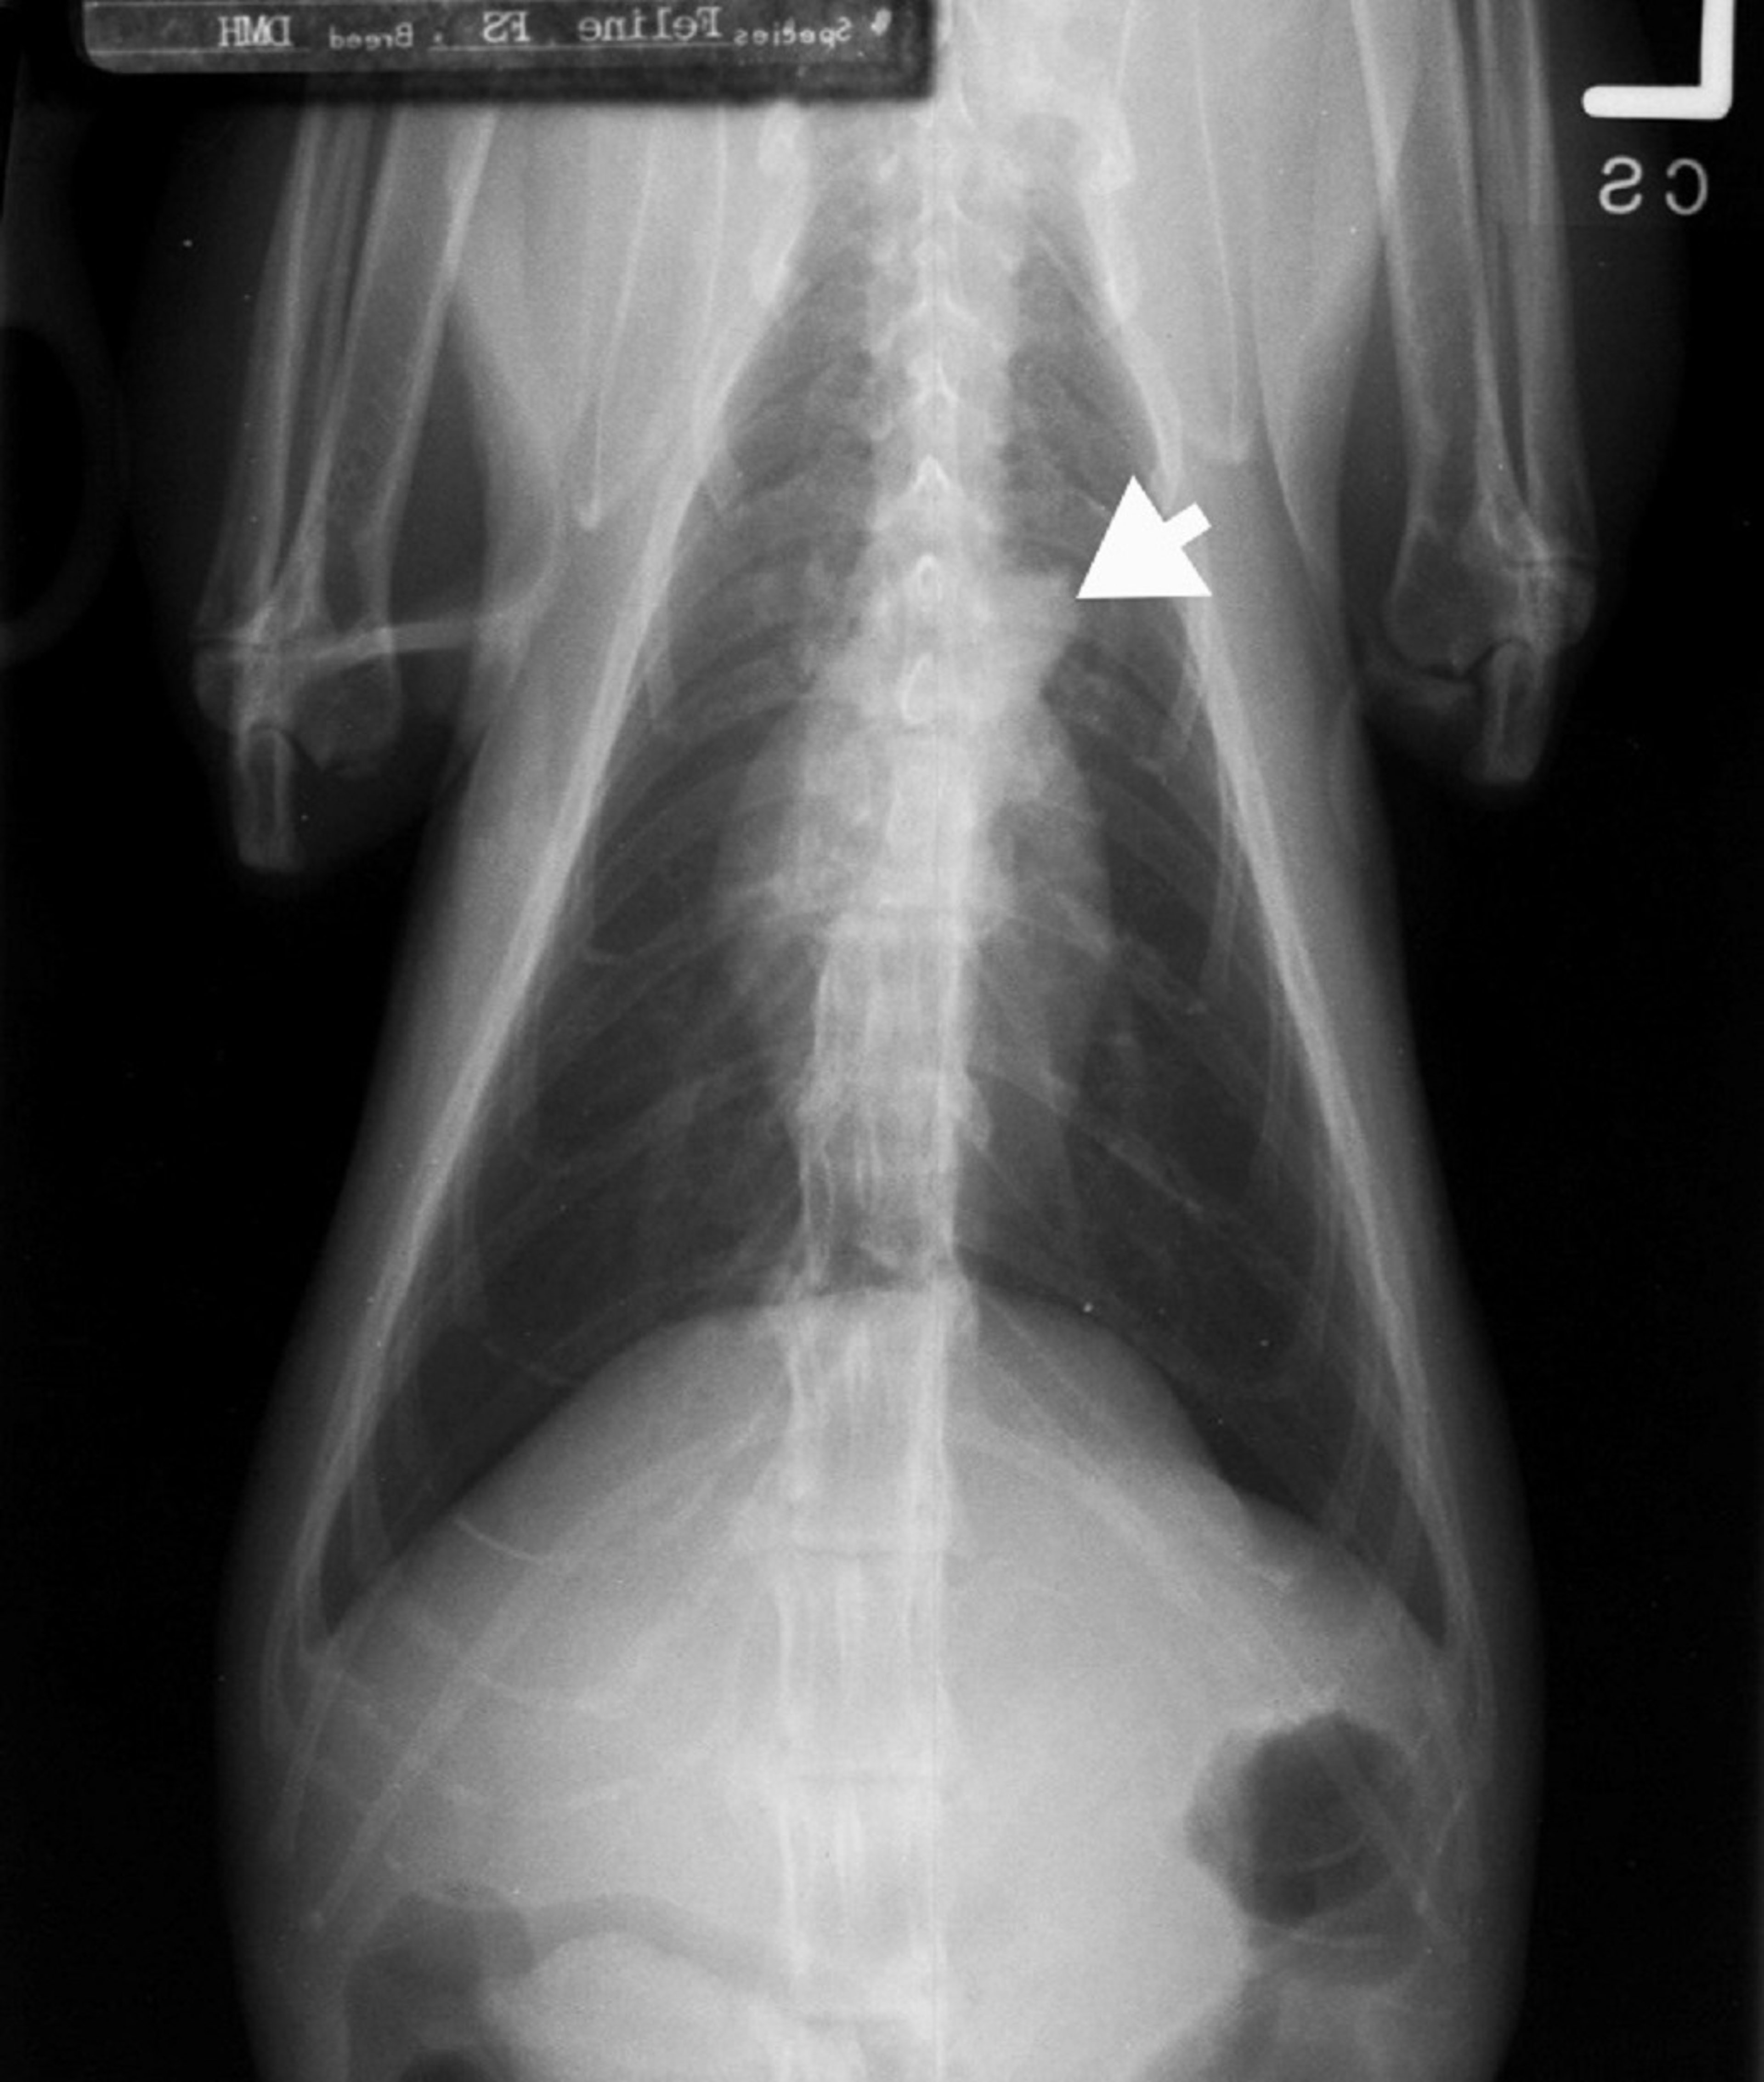

Radiografía ventrodorsal, gato normal de edad avanzada con "protuberancia" aórtica

Esta radiografía VD muestra la protuberancia aórtica (flecha) en un gato normal de edad avanzada.

Cortesía del Dr. Mark D. Kittleson.